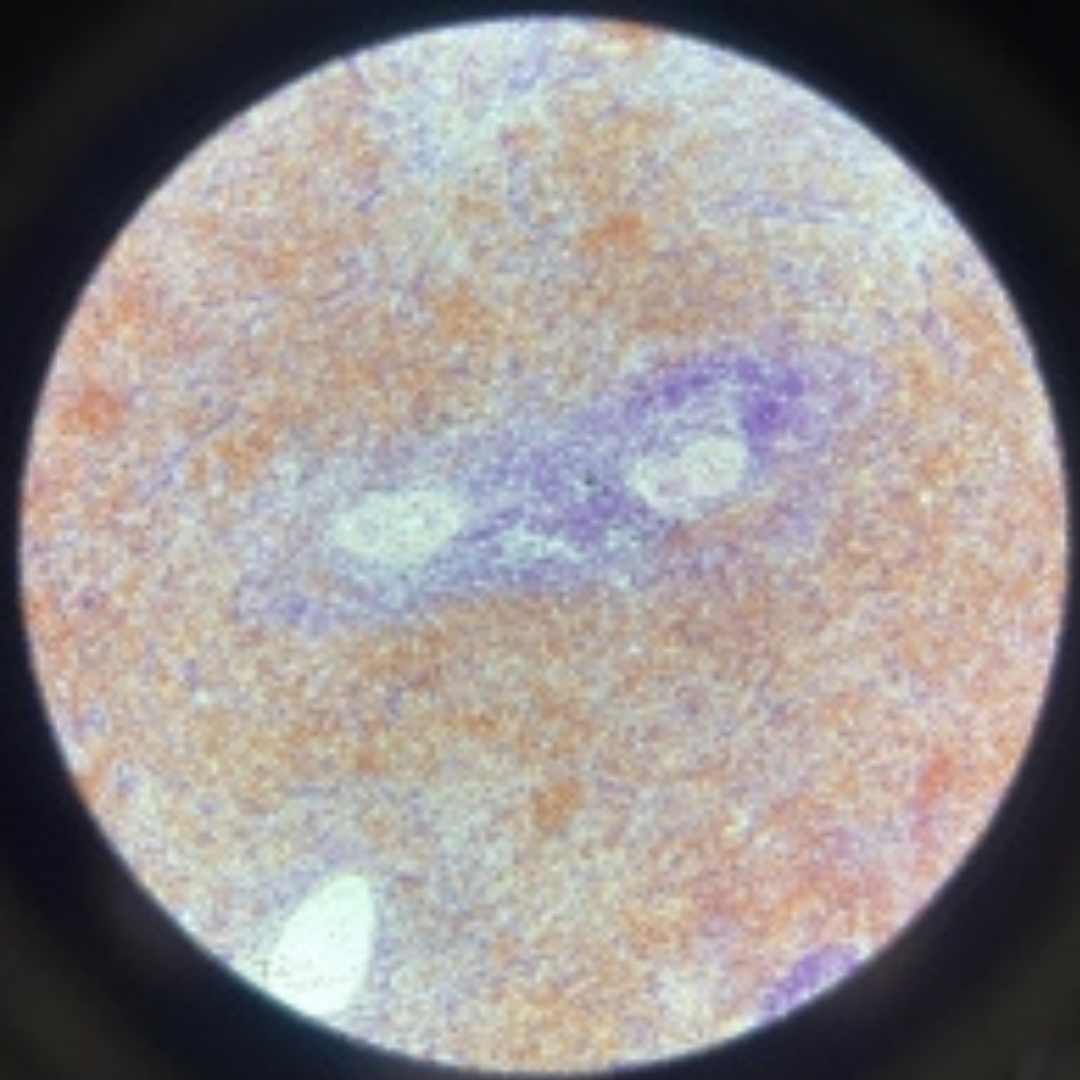

Spleen

21

New cards

Spleen

22

New cards

Spleen

23

New cards

Spleen

24

New cards

Spleen

25

New cards

Spleen

26

New cards

Spleen

27

New cards

Spleen

28

New cards

Spleen